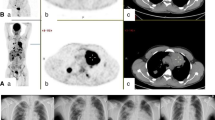

Adoptively transferred T cells migrate to tumor

Ten days after the last infusion, enlarged LNs were sampled to determine if the administered T cells migrated to sites of tumor. Under fluorescent microscopy, PKH-26+ T cells could be detected throughout a LN and this was concordant with the expression of CD3 ( Fig 4D ). Thus, we conclude that the infused T cells can traffick to and persist in, secondary lymphoid tissue containing tumor.

(a) Ratio of CD4:CD8 T cells in PB after CHOP, but before adoptive transfer of T cells and compared with measurements taken three hours after each T-cell infusion. The grey shaded area represents the mean CD4:CD8 ratio (1.6:1) in healthy subjects (n = 4). (b) Mean T-cell counts in PB from 6 canines before and after adoptive transfer of T cells. The grey shaded area represents the range for CD8+ T cells in healthy subjects (n = 4, 581 to 958 cells/µL). Arrows represent days T cells were infused. (c) Mean expression of CD3+ T cells pre-stained with red fluorescent dye, PKH-26, in the PB of 6 canines. Arrows represent days T cells were infused. (d) Evaluation of fluorescence and staining of CD3 from a LN biopsy. Frozen tissues were viewed with fluorescent microscopy to detect (top) PKH-26+ (red) T cells and (bottom) co-stained with anti-CD3 (black) to validate T-cell presence.